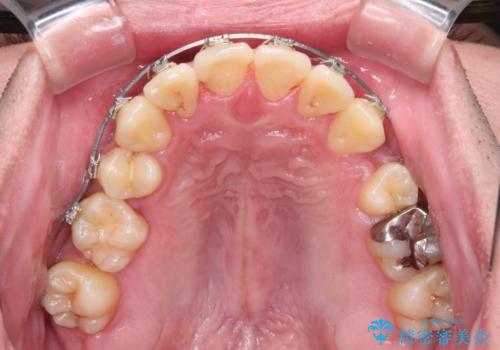

- メタルブラケット

- 治療期間

- 3年10ヶ月

右上第一小臼歯は歯根癒着により移動せず、左上第二小臼歯は移動はするものの非常に動きが鈍かったため、抜歯したスペースを閉じるまでに非常に時間がかかってしまいました。